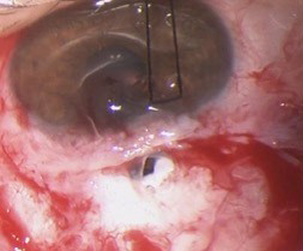

After two years, the patient attended our appointment due to low visual acuity. On examination, VA OD was 20/200, IOP was 5mm Hg with a thin, avascular and transudative bleb, visualizing the underlying uveal tissue with chorioretinal folds (Figure 3 [Fig. 3]). Connective tissue diseases were excluded.

Figure 3: Avascular bleb and visualization of the underlying uveal tissue